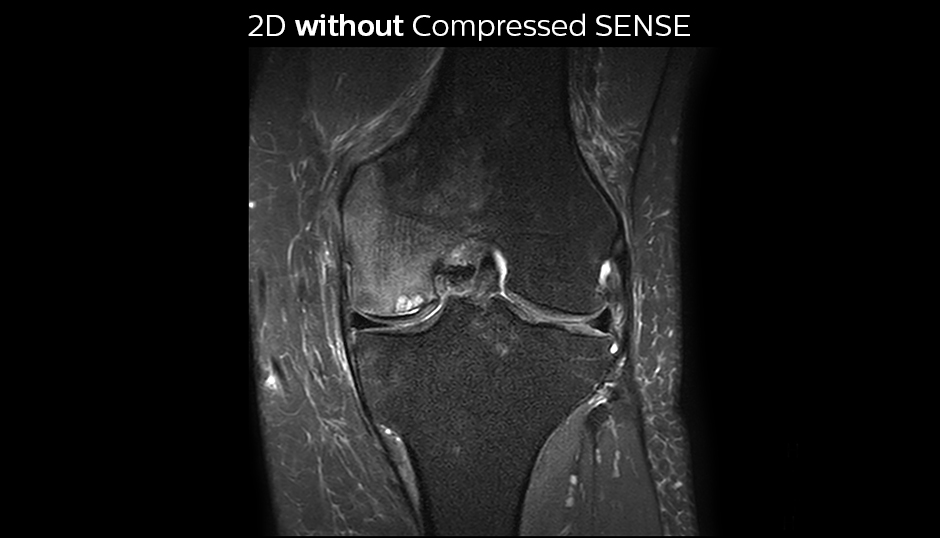

The KSW team also started implementing Compressed SENSE in ankle, elbow, knee and wrist MRI exams, for replacing the 2D PD fat sat with 3D PD fat sat. So far, results look good: it’s possible to obtain a good acquisition time with a high resolution.

A good acquisition time with high resolution is obtained when moving from three 2D acquisitions in three planes to one 3D acquisition with Compressed SENSE. In this example, Compressed SENSE with 3D VIEW PD SPAIR is 50% faster than three separate 2D scans and has improved spatial resolution.

Without Compressed SENSE Scan time 2:55 + 3:37 + 3:51 = 10:23 min. Voxel size 0.55 x 0.65 x 3 mm

Three separate 2D PD scans in three orientations